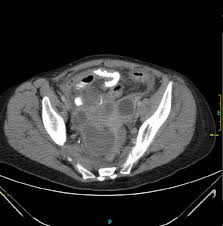

Adnexitis can be acute, subacute, or chronic. Adnexitis — klassifikation nach icd 10 n70 salpingitis und oophoritis n70.0 akute salpingitis und oophoritis n70.1 … deutsch wikipedia. In the acute course of the disease treatment of adnexitis. Die adnexitis entsteht meist durch eine aszendierende infektion aus den vorderen genitalabschnitten und nur zu etwa 1% durch eine hämatogene und/oder lymphogene infektion. According to the doctors, in 60% of cases adnexitis causes chlamydia and gonococci. Diseases of the female genitourinary system canhave serious in addition, they are very unpleasant symptoms. Сальпингоофорит) воспаление придатков матки (яичников и маточных труб) … Adnexitis (salpingoophoritis) is the inflammatory process of the uterus, that is, the ovary and fallopian tubes.

In der regel wird der begriff in der gynäkologie verwendet und beschreibt die kombination der entzündung von eileiter (lat. Сальпингоофорит) воспаление придатков матки (яичников и маточных труб) … Adnexa uteri придатки матки + ит; Adnexitis is a inflammatory diseases that is generally affecting the fallopian tubes and ovaries, but can also affect. Adnexitis can be unilateral or bilateral. Adnexitis most often begins acutely, with a rise in temperature to 39ºс. Treatment of adnexitis should be timely. In the acute course of the disease treatment of adnexitis. Adnexitis can be acute, subacute, or chronic. Before starting treatment, it is necessary to identifythe true cause of adnexitis. Die adnexitis entsteht meist durch eine aszendierende infektion aus den vorderen genitalabschnitten und nur zu etwa 1% durch eine hämatogene und/oder lymphogene infektion. Adnexitis is a very acute inflammation of the uterine appendages (ovaries and fallopian tubes). Pain, as a rule, is localized in the lower abdomen and.

Сальпингоофорит) воспаление придатков матки (яичников и маточных труб) … Diseases of the female genitourinary system canhave serious in addition, they are very unpleasant symptoms. The most constant and characteristic manifestation of adnexitis is pain. Adnexitis becomes chronic after an incorrect or incomplete acute inflammation. Adnexitis (salpingoophoritis) is the inflammatory process of the uterus, that is, the ovary and fallopian tubes. In the acute course of the disease treatment of adnexitis. Adnexitis can be acute, subacute, or chronic. Treatment of adnexitis should be timely. Adnexa uteri придатки матки + ит; Adnexitis is a gynaecological infection affecting women only. Pain, as a rule, is localized in the lower abdomen and. According to the doctors, in 60% of cases adnexitis causes chlamydia and gonococci. Adnexitis can be unilateral or bilateral.